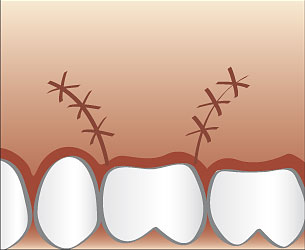

Ablauf einer Wurzelspitzenresektion

Üblicherweise wird eine Wurzelspitzenresektion in örtlicher Betäubung durchgeführt. Die Schleimhaut wird vom Knochen abgelöst und die Wurzelspitze mit Hilfe eines Spezialbohrers freigelegt. Anschließend wird die Wurzelspitze abgetragen und der Entzündungsherd oder eine eventuell vorhandene Zyste entfernt. Eine antimikobielle photodynamische Therapie mittels Softlaser kann für eine zusätzliche Keimreduktion sorgen. Bei Bedarf werden die dünnen Kanäle im Bereich der Wurzelspitze mit speziellen Ultraschallgeräten erweitert mit einem speziellen Füllungszement abgedichtet. Danach wird dessen Dichtheit überprüft und die Schleimhaut vernäht.

Wie bei allen operativen Eingriffen erhalten Sie nach der Operation ausführliche individuelle auf Sie abgestimmte Tips darüber wie Sie sich während der folgenden Tage verhalten sollten.